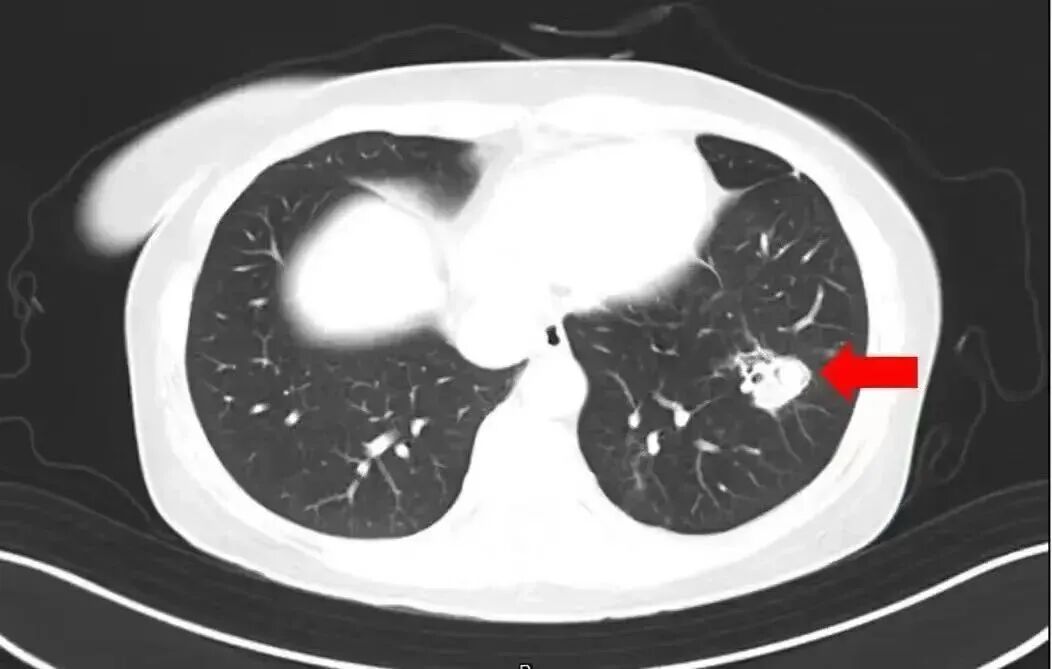

近日,一6岁女童因持续发烧17天且意识不清,被转至郑州郑大一附院治疗。医生检查后大吃一惊:孩子脑子竟被“啃”出大大小小十几个洞,再晚来几天可能会被“啃空”。抽取洞内积液检测后,医生锁定了“真凶”——烟曲霉菌。

医生介绍,烟曲霉菌常隐藏在潮湿环境中,孩子在此玩耍后,霉菌通过呼吸道进入血液系统,进而“爬”进了脑子。